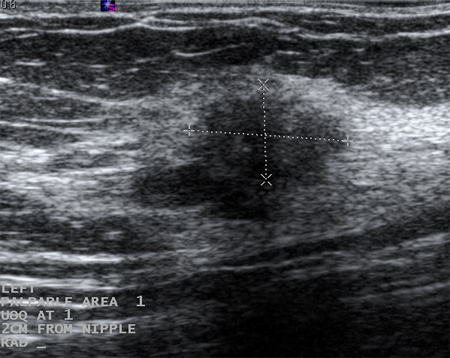

Cysts that recur or do not completely resolve with aspiration should be biopsied to rule out malignancy. Similarly, biopsy should be considered in complex cysts or those with solid elements. Sonographic characteristics may classify a solid mass as either "probably benign" or "suspicious." Masses that are smooth, oval, lobulated, with clearly defined margins, and that are wider than they are tall, are often benign (e.g., fibroadenoma). If a mass is irregular, heterogeneous, has poorly defined or spiculated margins, and is taller than it is wide, it is considered "suspicious" for malignancy, and biopsy should be undertaken.[Figure caption and citation for the preceding image starts]: Ultrasonographic image of a complex cystCourtesy of Dr Lane Roland, University of Louisville; used with permission [Citation ends].

[Figure caption and citation for the preceding image starts]: Ultrasonographic image of an invasive carcinomaCourtesy of Dr Lane Roland, University of Louisville; used with permission [Citation ends].